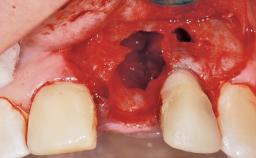

Immediate Placement of an Implant in a Maxillary Right Central Incisor Site

A 30-year-old female patient was referred to the office for the treatment of tooth 11. Her chief concern at the initial visit was to inquire, “Why is my tooth pink?” Upon clinical examination, it was determined that tooth 11 had a previous history of trauma and that the clinical crown had become noticeably pink in color as a result of internal resorption. This diagnosis was confirmed radiographically, indicating a large radiolucency involving the central and distal portions of the clinical crown. It was determined that restoration of this tooth was not possible, and that extraction was indicated. The presence of a mid-line diastema, which the patient wanted to reproduce, directed the treatment plan for tooth replacement utilizing a dental implant.